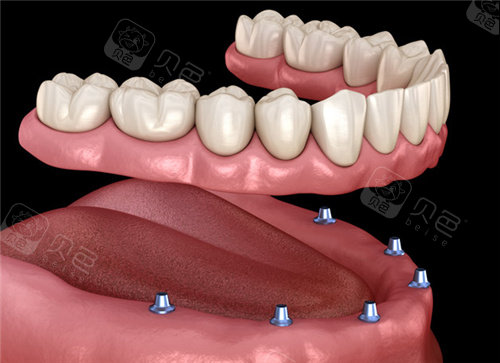

all-on-4半口种植牙示意图

图片尺寸500x333